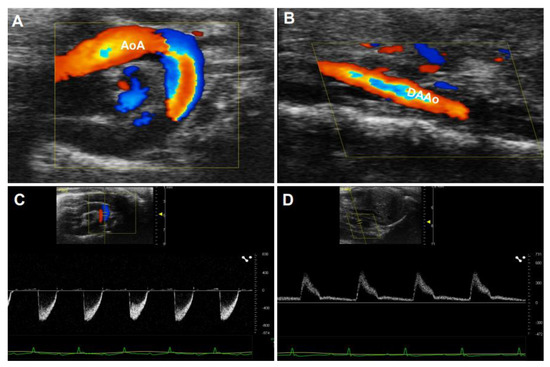

Doppler ultrasonography employs the Doppler effect to generate imaging of the movement of tissues or body fluids (usually blood) and their relative velocity to the probe. By calculating the frequency shift of a particular sample volume, its speed and direction can be determined and visualized. There are several applications with Doppler ultrasonography, such as CD, SD, and tissue Doppler images (TDI). While CD ultrasonography provides an image showing blood flow by the bright areas of aliasing (Figure 5A–C) and turbulence in the aorta’s narrowed segment, SD imaging provides quantitative data on blood velocities, enabling flow volumes and pressure gradients to be calculated (Figure 5D–F). An important characteristic of the waveform is the peak systolic velocity, which increases as the luminal diameter decreases, such as in the setting of stenosis. Vessel tortuosity and branching can lead to either focally increased or decreased velocity, resulting in a flow disturbance or even flow reversal [50]. These characters of Doppler images are similar in humans (Figure 5A–F) and rodents (Figure 6A–D).

Figure 6. Color Doppler(CD) and pulsed-wave images from a mouse aorta. The representative images by CD were obtained from a healthy four-month-old C57BL/6J mouse. (A,B): CD images of the aorta arch (AoA) (A) and descending abdominal aorta (DAAo) (B). (C,D): The corresponding Inflow velocity of (A,B) using pulsed-wave Doppler imaging.